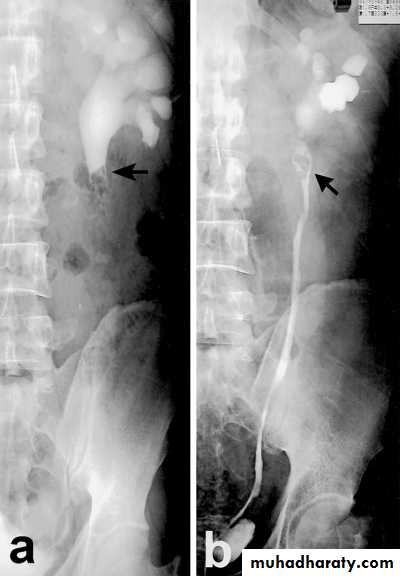

Failure of contrast to pass to ureters due to both sided mid ureteric stones

LT sided upper Ureteric stones

Bilateral HU + HN